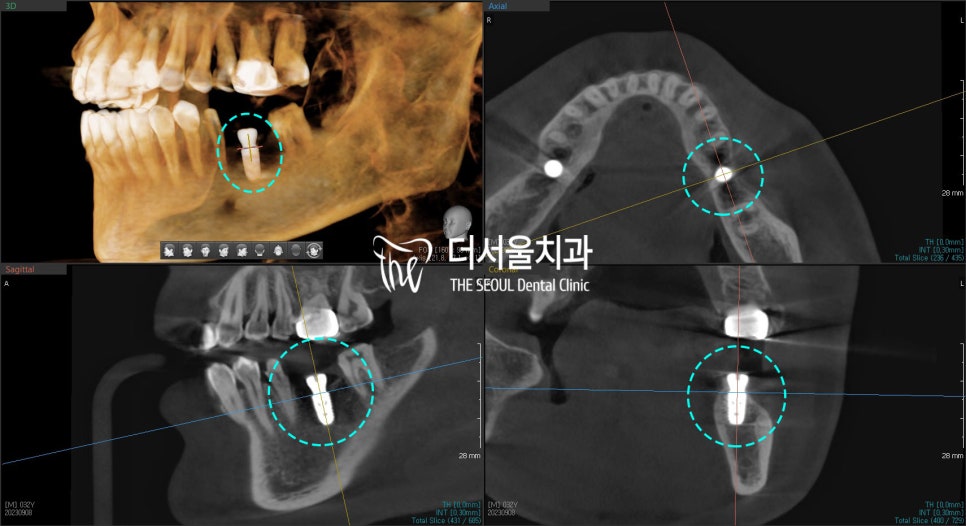

가이드를 이용하여

픽스처를 잘 식립하였으며

성남 치과의원 에서는

CT를 촬영하여

치조골 내 중간에 잘 고정되었는지

한 번 더 확인합니다.

이 과정을 통해

방향, 깊이, 간격 같은

여러 요소를 좀 더

디테일하게 확인할 수 있습니다.